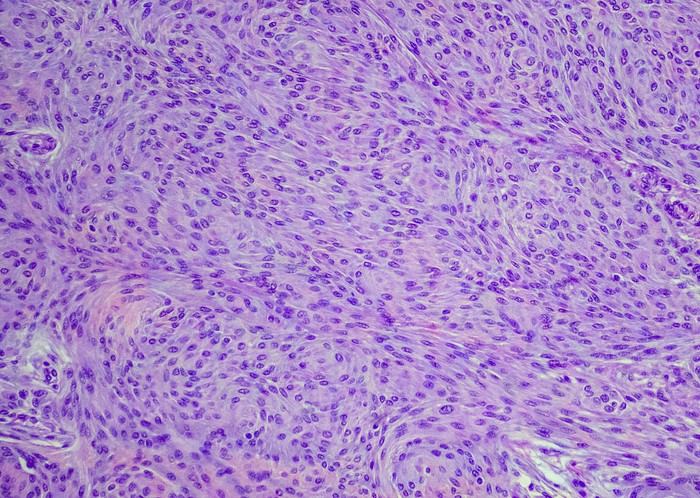

Featured photo at top of meningioma cells. Photo/OGphoto/iStock.

Brain or spinal cord tumors called meningiomas can cause visual impairment, which is sometimes severe and permanent, that can be used as a surrogate for analyzing tumor growth.